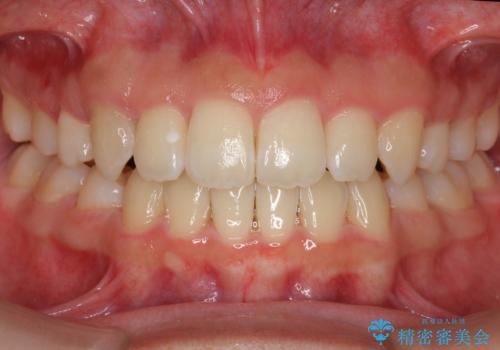

上下前歯が接触しない オープンバイトをインビザラインで改善

オープンバイト(開咬)を非抜歯インビザラインで治す